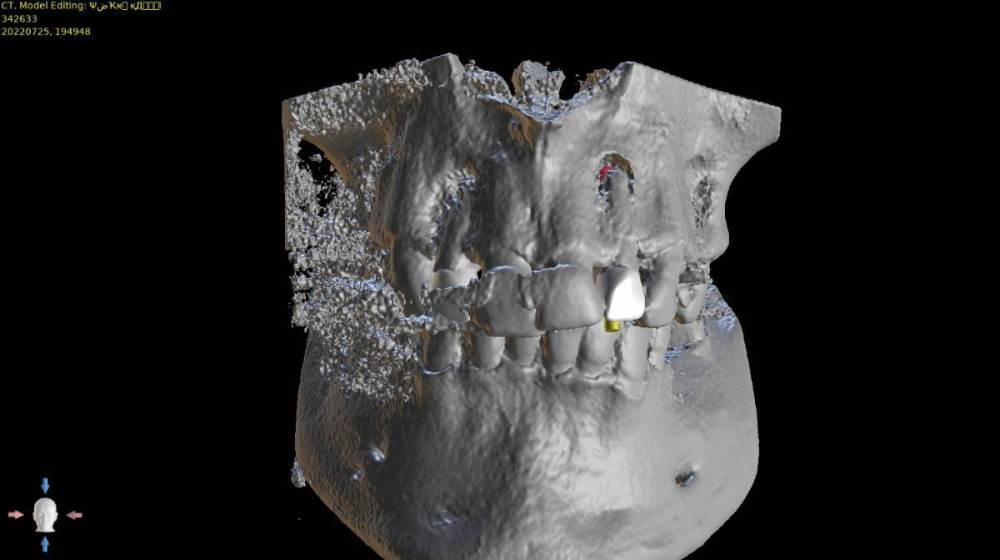

Женька Опубликовано 6 августа, 2022 Поделиться Опубликовано 6 августа, 2022 В общем планируется большая (по крайней мере для меня) работа. Вот такой товарищ у нас. Делали бы НКР в области 2.5з? или поставили бы чисто по кости, а оголённый участок закрыли присыпкой и мембраной? Также вопросы по двойкам имеются. Бугор есть, сразу оговорюсь, правда только с одной стороны. Также не понятно пока "как его правильно готовить" этот бугор, чтобы закрыть такие дефекты вестибулярной пластинки. Скрины постарался нарезать по максимуму. Там ещё будет ортодонтия конечно же. Интрузии, движения всякие и тд) Да, знаю, что планировать без цифрового гипса неправильно, но что имею. Ссылка на комментарий

Женька Опубликовано 6 августа, 2022 Автор Поделиться Опубликовано 6 августа, 2022 (изменено) @Irouil ортопед вряд ли согласится на такое. Может тогда проще пойти отсроченно? Удалить, кюретаж, губку в лунки и мэриленд (каппа с зубами) на 3 месяца. А потом уже выдумывать пластики по факту новой КТ? Винты 14мм максимум что есть По премоляру вот тоже думаю, что игра не стоит свеч. А двойки... признаться я уже ортопеду сказал, что отсрочено пойдём... хотя конечно пока всё ещё раздумываю Изменено 6 августа, 2022 пользователем Женька Ссылка на комментарий